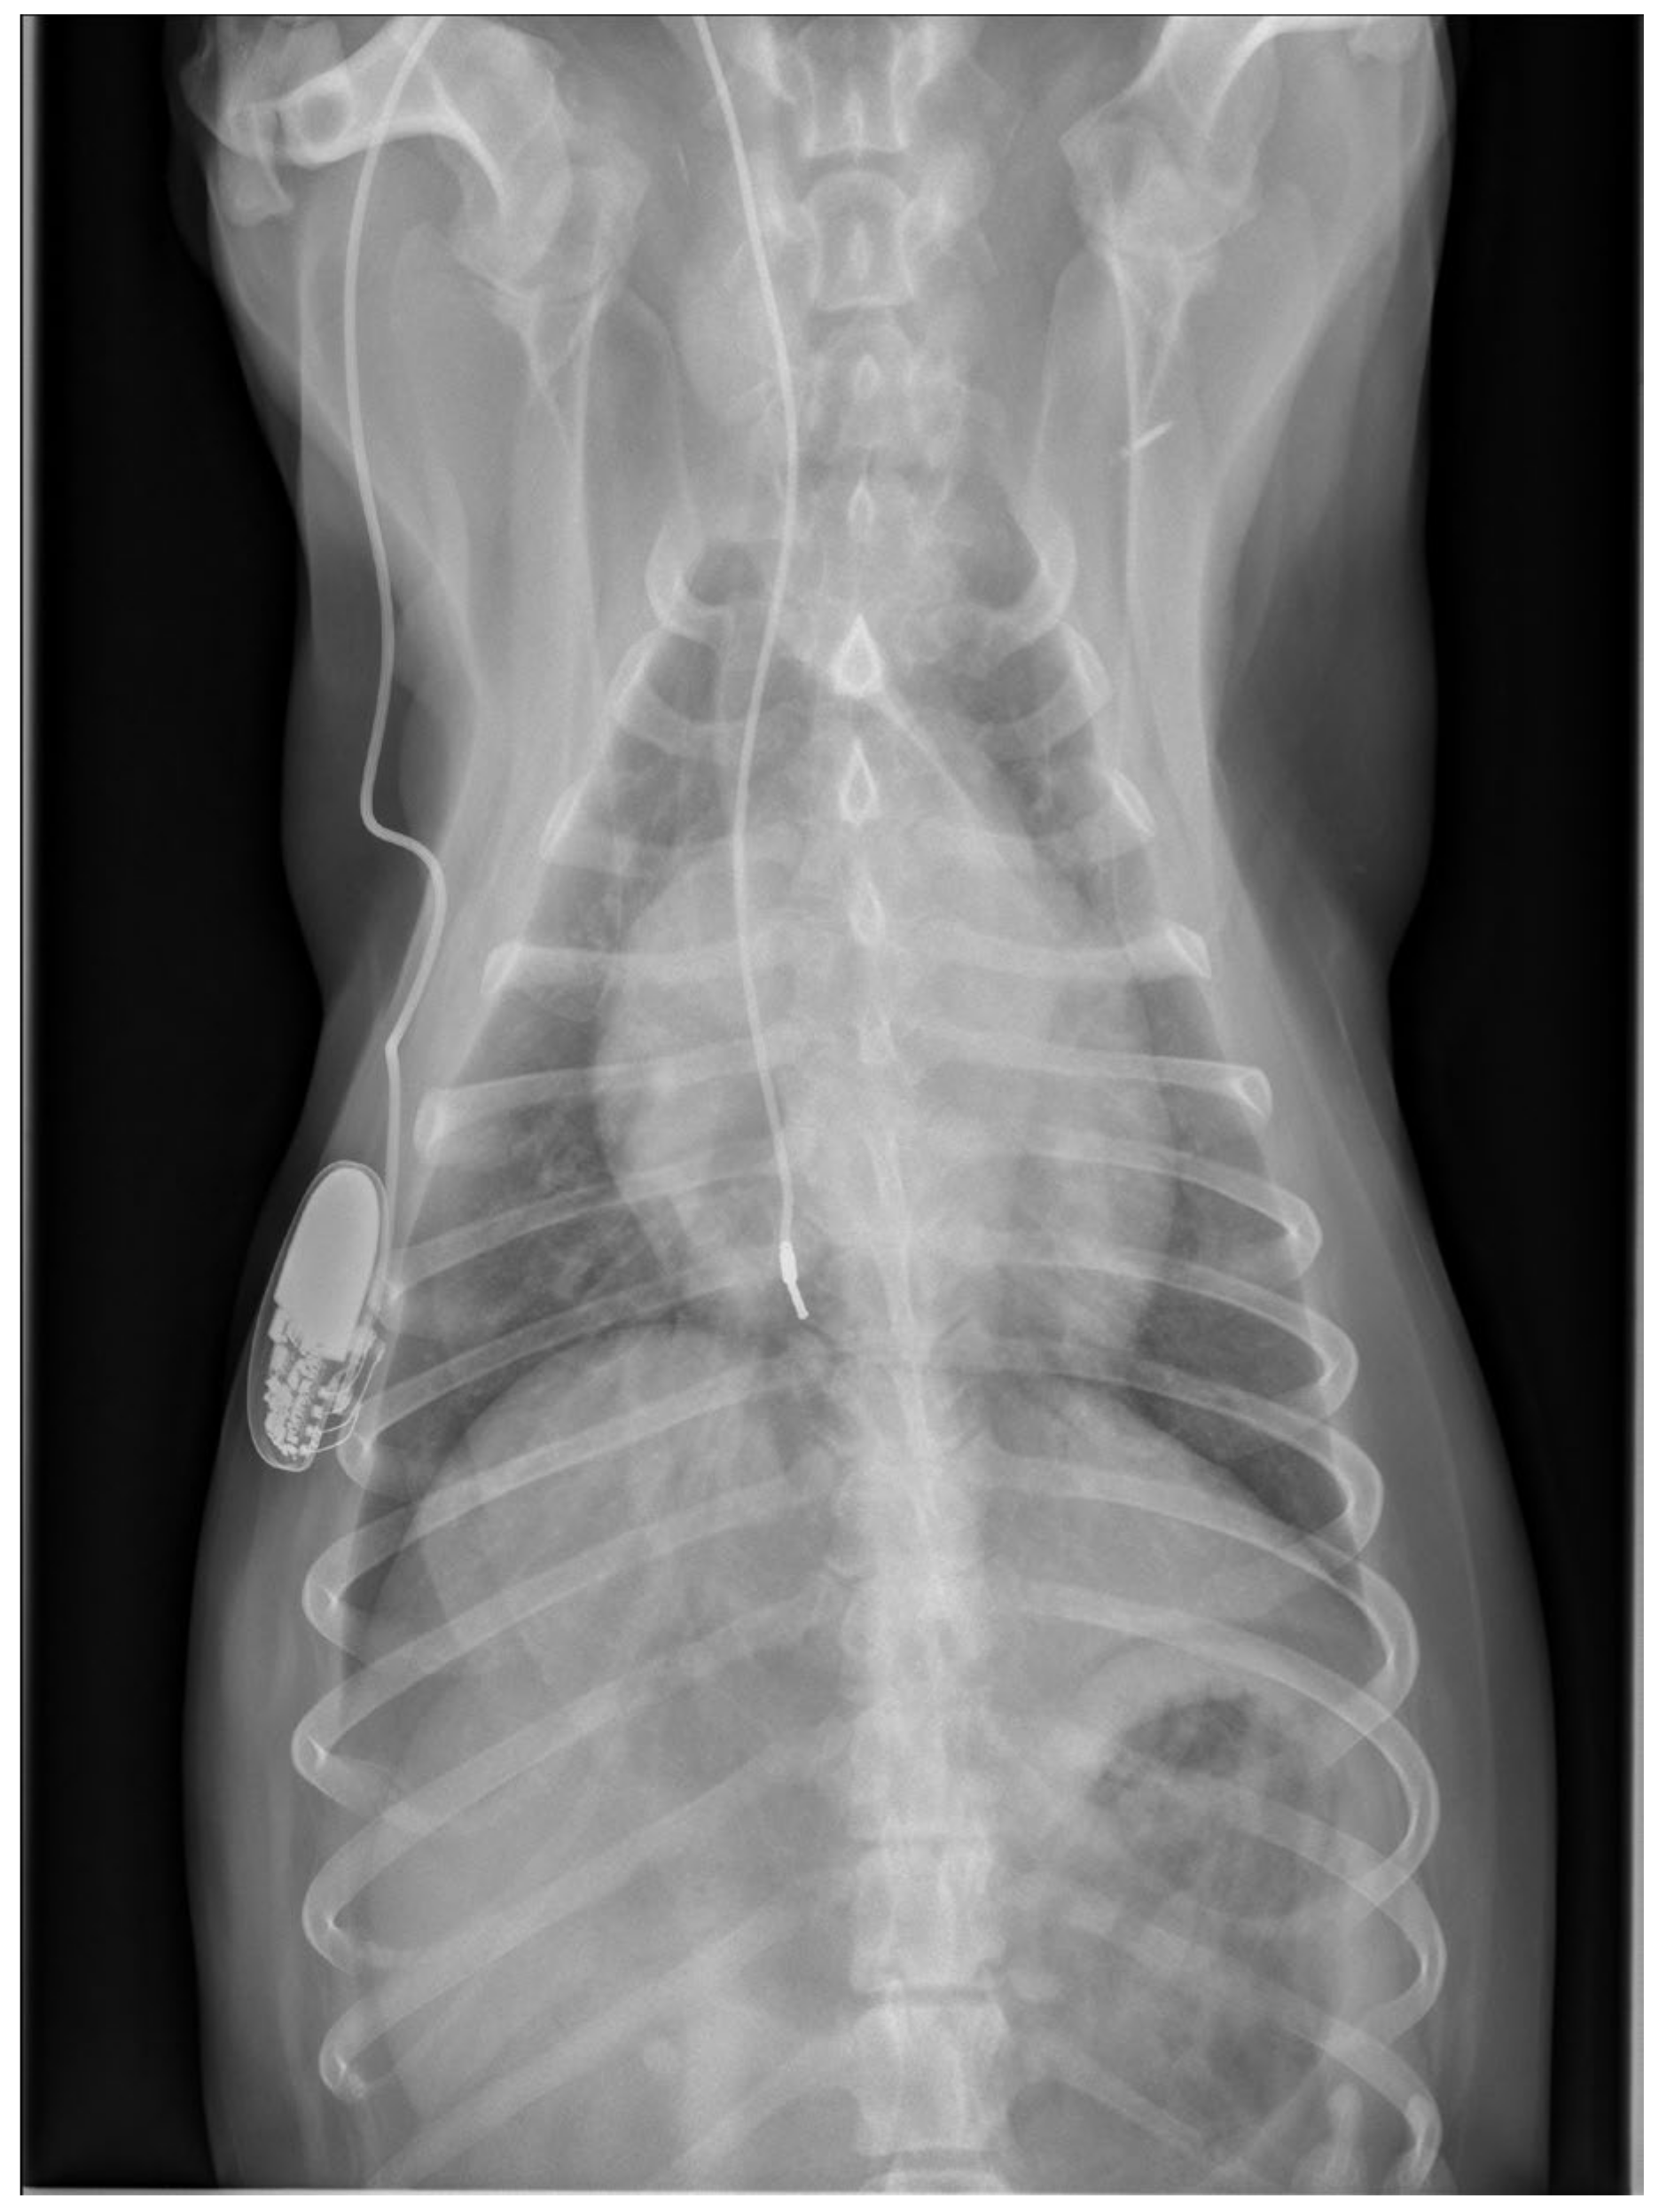

Physical examination at the authors’ institution, three years after the pacemaker implantation, revealed a bright, alert and responsive dog with a respiratory rate of 60 breaths/min and a pulse rate of 44 beats/min. The rectal temperature was 39.5 °C. The dog had received the last dose of antibiotics a day previously. Thoracic radiographs, an electrocardiogram, an echocardiogram, an abdominal ultrasound examination, urinalysis, and feces and blood tests were performed in order to identify the cause of the cough, hyperthermia and bradycardia. Thoracic radiographs showed no abnormalities and the position of the pacemaker lead was identical to that of the radiographs performed immediately after implantation (Figure 2). Electrocardiography showed a good functioning pacemaker, and ventricular premature complexes with periods of ventricular tachycardia (Figure 3 and Figure 4), which were assumed to have caused the pulse deficit.

Figure 2.

Thoracic radiographs of a dog with chronic cough, hyperthermia and increased respiratory rate show no pulmonary pathology and unchanged position of the pacemaker electrode compared to the direct post-operative radiographs.

At the next check-up a week later, the owner reported a gradual worsening of appetite and exercise tolerance, while frequent coughing remained unchanged. Every coughing episode was followed by gagging. In addition, the owner reported an increased respiratory rate at rest, frequent panting, and episodes of weakness during walks. Physical examination revealed a slightly depressed dog with an increased respiratory effort and a respiratory rate of 52 breaths/min. The femoral pulses were irregular with a rate of 60 beats/min. Rectal temperature was 38.6 °C. Thoracic radiographs were repeated, which showed a mild diffuse broncho-interstitial lung pattern, sternal lymphadenopathy and increased diameter of the lobar pulmonary arteries to the right cranial and right caudal lung lobes (Figure 6).

Figure 6.

Thoracic radiographs of a dog with chronic cough, hyperthermia and increased respiratory rate and effort show unchanged position of the pacemaker electrode compared to the direct post-operative radiographs. The open arrows indicate the prominent pulmonary artery branches to the right cranial and right caudal lung lobes.